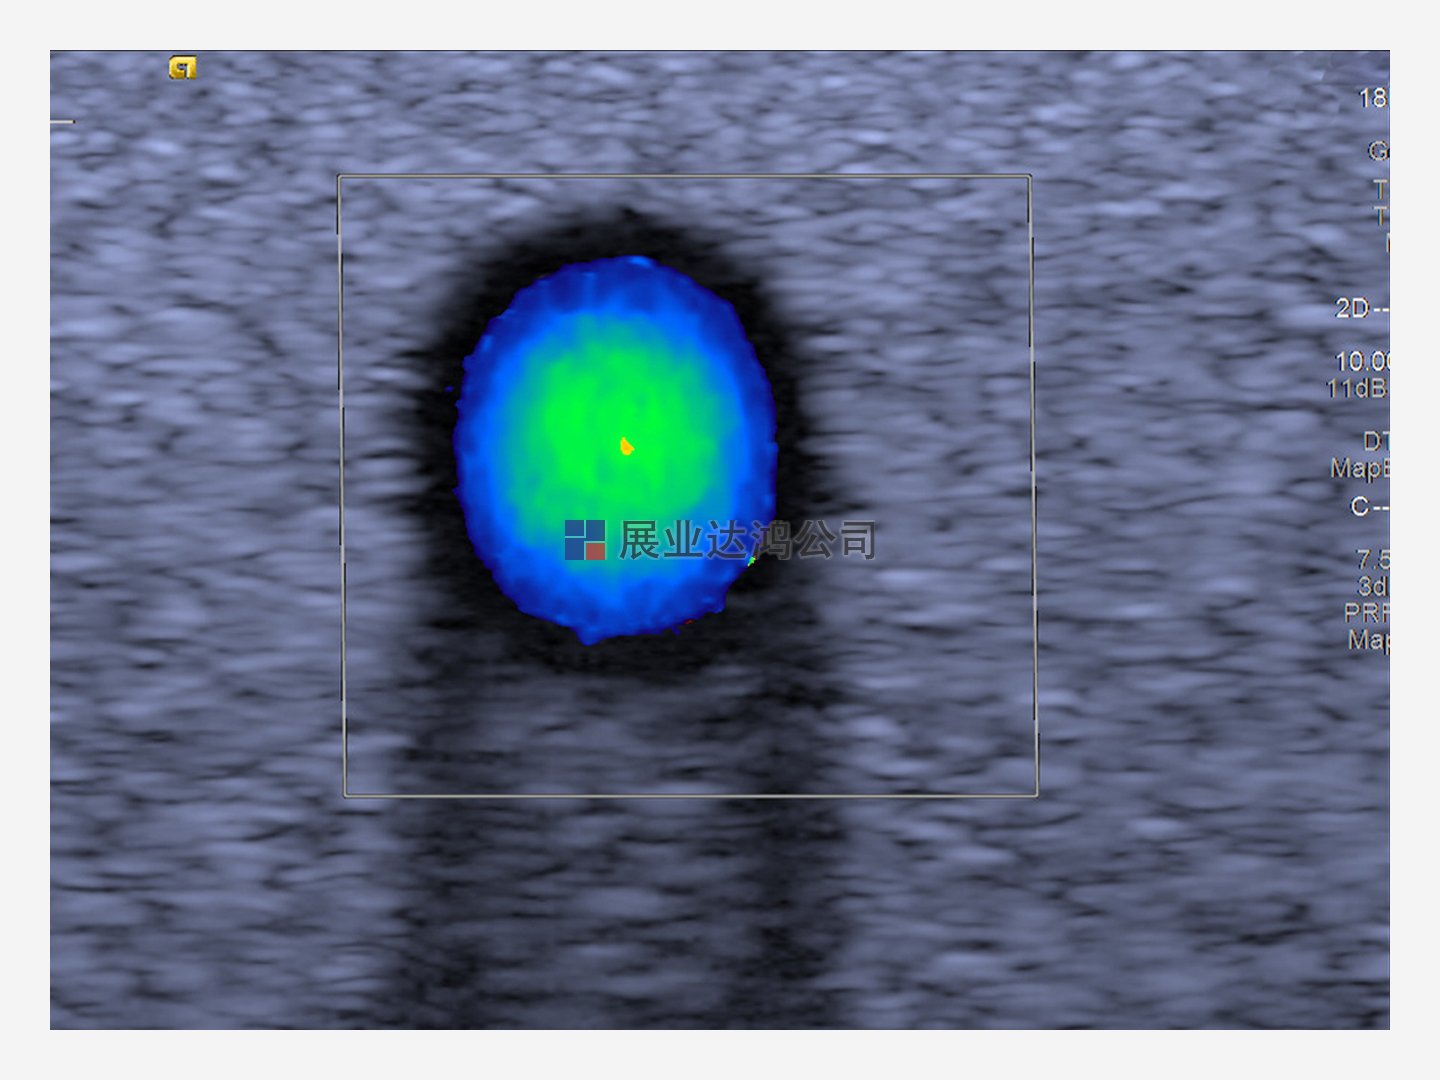

我們的模型包含類似于人體組織的超聲波模擬血液,電子流為 1550 m/s。獲得專利的高當(dāng)量凝膠 (HE Gel™) 提供組織模擬,用于評估圖像均勻性、檢測失效的換能器元件和評估最大穿透深度。

橫截面圖像顯示了管道中心的最高速度,代表了層流拋物線流的測量